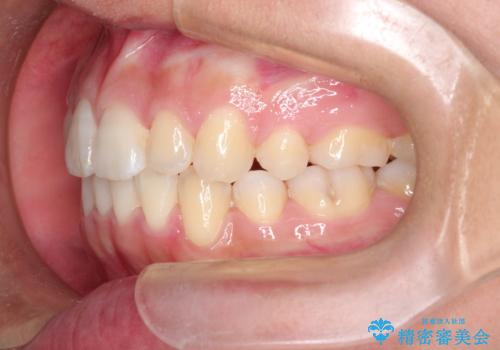

- 前歯のガタガタを主訴に来院されました。

前歯の重度のガタガタで、八重歯もある状態でした。

また右下の乳歯が残っており、永久歯が1本足りませんでした。

上顎両側と左下の前から4番目の歯と、右下の乳歯を抜歯して矯正することとなりました。